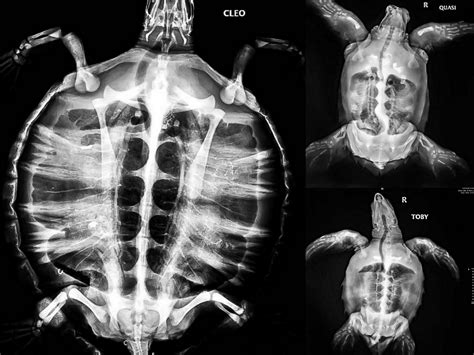

One of the most immediate and striking things you’ll see in x-ray images of turtles is their incredible skeletal structure. The shell itself isn’t just a hard outer casing; it’s actually an integral part of the turtle’s skeleton! The carapace (the top part of the shell) and the plastron (the bottom part) are formed from fused ribs, vertebrae, and dermal bones. When you look at an X-ray, you can clearly see how these bones are connected and how they integrate with the rest of the skeleton, including the limbs and the skull. This detailed view is super useful for diagnosing any kind of trauma. Did the turtle get into a fight with another turtle? Did it fall from a height? An X-ray can reveal hairline fractures, displaced bones, or even significant breaks in the shell or limbs that might not be visible on the outside. This level of detail allows veterinarians to plan the best course of action for healing, whether it’s simple rest or more complex surgical intervention. Furthermore, understanding the normal skeletal development in different turtle species is crucial. For young turtles, X-rays can help assess growth patterns and detect any congenital abnormalities. For adult turtles, it helps us understand their baseline anatomy, which is essential for monitoring their long-term health and for research purposes. We can literally see the foundation upon which their entire body is built, offering a unique perspective on their resilience and biological design. It’s a testament to how evolution has created such a unique and effective protective system, and X-rays give us the power to appreciate its complexity.

Beyond the bones, x-ray images of turtles are absolute lifesavers when it comes to diagnosing internal health issues. Turtles, like any animal, can suffer from a range of problems that aren’t visible from the outside. One of the most common and heartbreaking issues we see is the ingestion of foreign objects, particularly plastic. Turtles often mistake plastic bags for jellyfish or other food sources, and these items can become lodged in their digestive tract, causing blockages, internal injuries, and even death. An X-ray is often the quickest and most definitive way to confirm the presence of such an object and determine its location. We can also use X-rays to look for signs of organ damage or disease. For instance, an enlarged heart might indicate cardiac issues, or changes in the appearance of the lungs could point to respiratory infections like pneumonia, which are unfortunately common in aquatic turtles. Kidney or bladder stones can also be visualized. In females, X-rays are indispensable for assessing reproductive status. We can count and evaluate the development of eggs, check for egg binding (where eggs fail to be laid), or identify any abnormalities within the reproductive tract. This information is vital for both treating sick individuals and for understanding the reproductive biology of different species, which is crucial for conservation. The ability to see these internal issues non-invasively means we can intervene earlier, increasing the chances of a successful recovery and minimizing stress on the animal. It’s a powerful tool for proactive and reactive veterinary care.